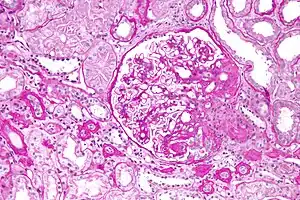

| Light micrograph of focal segmental glomerulosclerosis, hilar variant. Kidney biopsy. PAS stain. | |

The individual components of the name refer to the appearance of the kidney tissue on biopsy: focal—only some of the glomeruli are involved (as opposed to diffuse), segmental—only part of each glomerulus is involved (as opposed to global),[19] glomerulosclerosis—refers to scarring of the glomerulus (a part of the nephron (the functional unit of the kidney)). The glomerulosclerosis is usually indicated by heavy PAS staining and findings of immunoglobulin M (IgM) and C3-convertase (C3) in the sclerotic segment.[20]